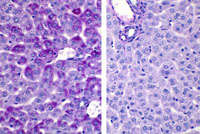

Periodic acid Schiff stain of glucose-6-phosphatase +/+ mouse (left) and -/- mouse (right) showing glycogen storage in hepatocytes of formalin fixed liver.